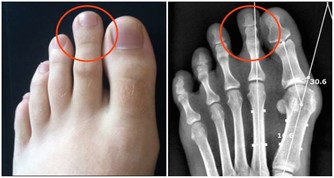

有發疹、劇烈頭痛、關節痛、痙攣症狀。

第一,胳膊、腿麻木、刺痛,精神紊亂、暈眩,說話打顫、語無倫次。尤其是面部或者身體一側出現上述情況,就可能是中風,也就是腦卒中的前兆,預示向大腦供氧的動脈堵塞或者破裂。如果是大動脈出問題,大腦中很大一部分就會受到影響,進而導致半身麻痺,同時失去講話等功能。如果是小血管出問題,胳膊或腿會麻木。出現上述症狀應立刻就醫。一般說來,血栓發生三小時內是治療的最佳時機。

第四,腿肚子酸痛、胸痛、氣短、咳血。這些是危險的腿部血栓形成前兆。久坐之後最易發生,手術之後長時間臥床,也會出現這種症狀。人人都可能得這種病,坐臥時間久了,血液淤積在腿部,腿部出現血栓,小腿肚子腫疼,此時如果突然出現胸痛或者氣短,說明血栓可能已經脫落並通過血液進入肺部。那可是萬分危險,要立刻去醫院。